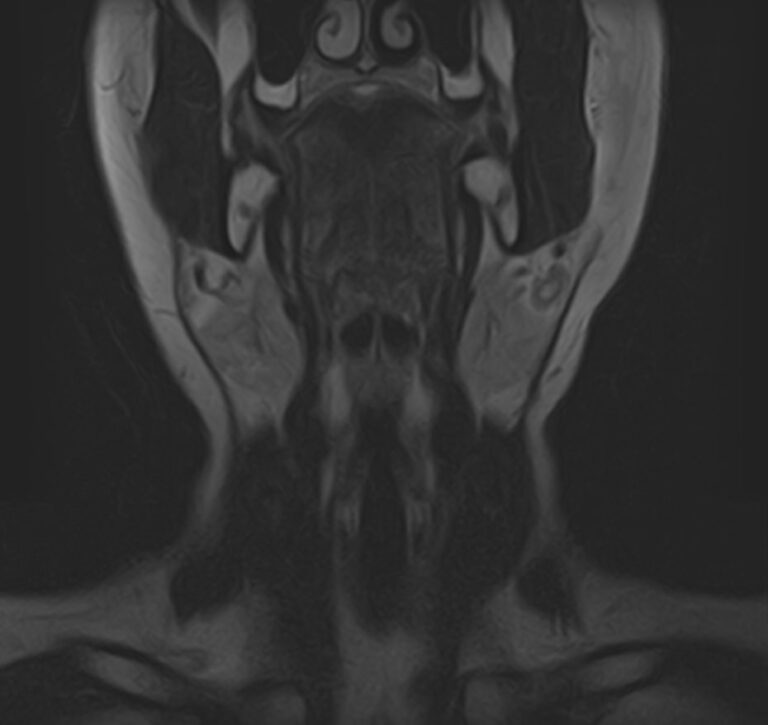

Магнитно-резонансная томография шеи предусматривает детальную визуализацию различных анатомических структур области шеи. Сюда входит полость рта, язык и корень языка, пищевод, гортань, окологлоточные лимфоузлы, шейные лимфоузлы, слюнные железы, щитовидная железа, мышцы и межфасциальные пространства.

В нашей клинике данное обследование выполняется на новейшем 32-канальном высокопольном томографе закрытого типа TOSHIBA VANTAGE TITAN 1,5 Тесла. Высокотехнологичный аппарат производит сканирование путем тончайших срезов с шагом от 1 мм в трех различных плоскостях. Используя современные компьютерные программы, полученные данные преобразуются в 3D-изображение исследуемой зоны. Это обеспечивает точность и достоверность диагностики заболеваний анатомических структур, расположенных в области шеи.